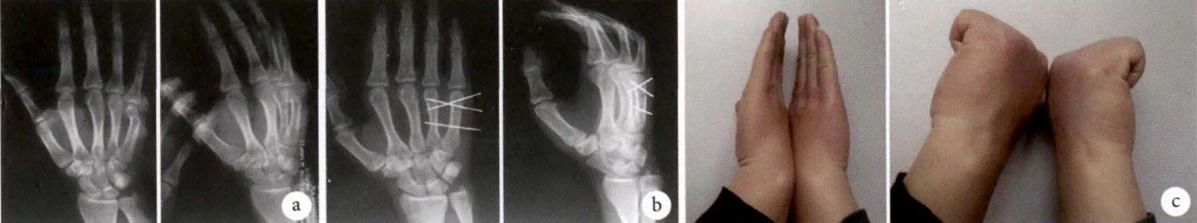

На снимке выше показано лечение перелома шейки пятой пястной кости с закрытой репозицией, чрескожной поперечной фиксацией спицами Киршнера.

Больной, мужчина, 20 лет, получил боксерскую травму, повлекшую за собой перелом шейки пятой пястной кости правой руки. а. Предоперационная рентгенография; б. Рентгенограмма через 1 неделю после операции; в. Функциональное положение руки через 13 месяцев после операции (из ссылки 14)